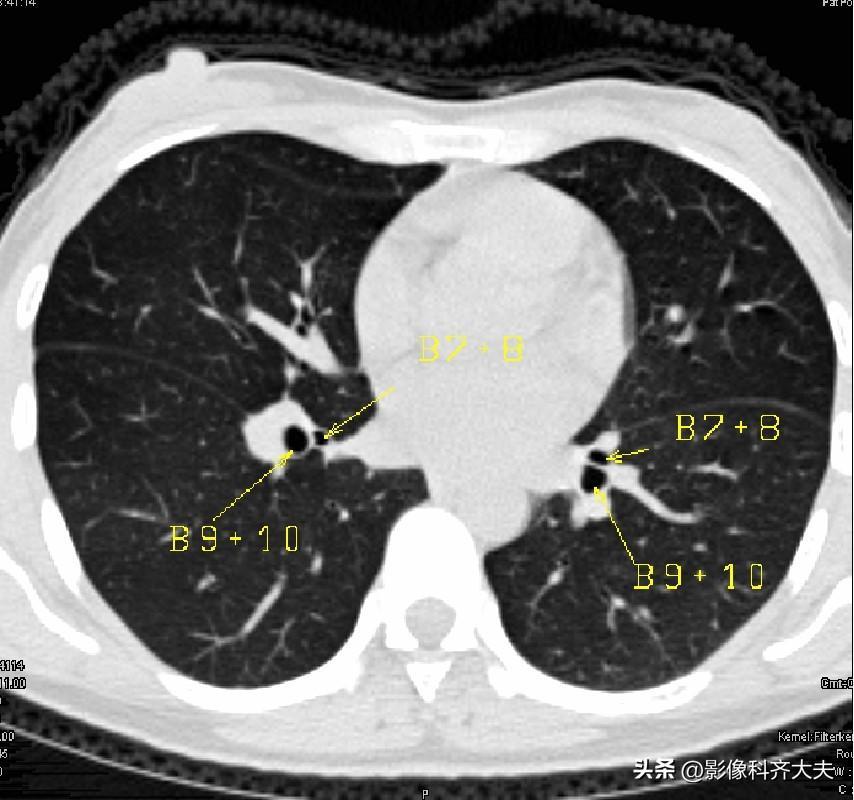

图15-近心底层面

▲B7+8:下叶前内段支气管